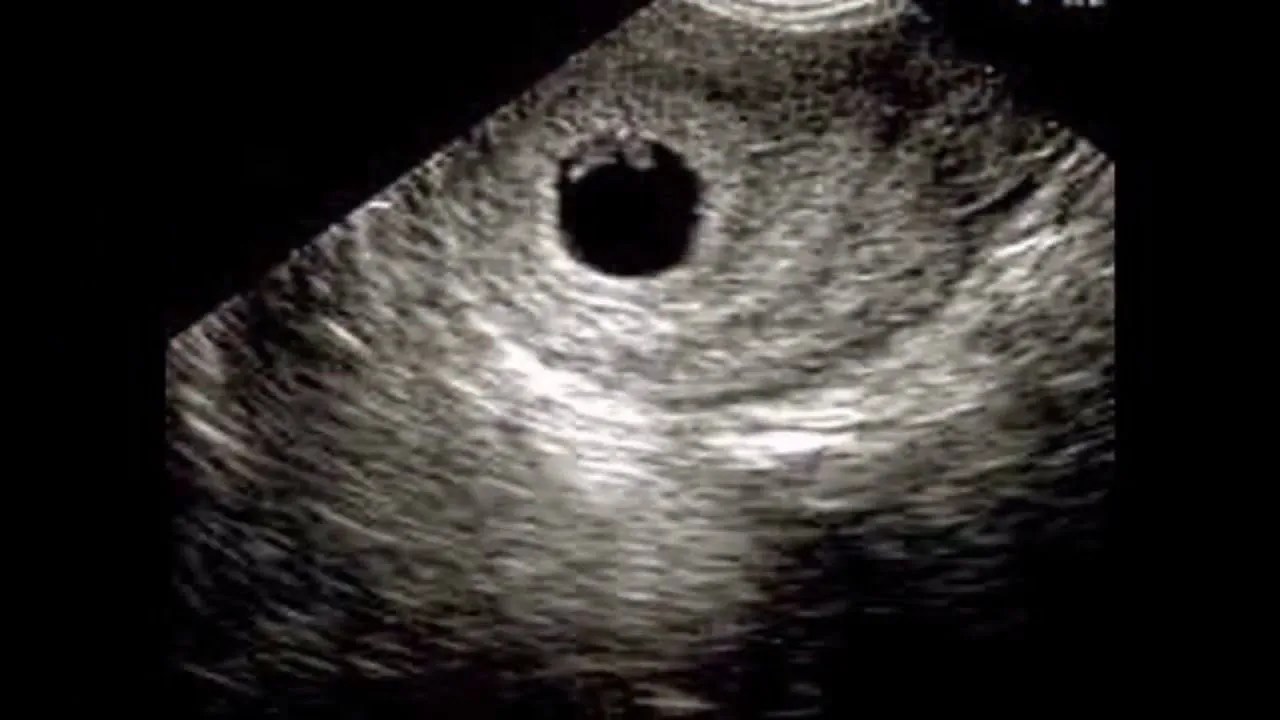

وقبل التعرف على متى يظهر الجنين في السونار، بالتالي فإن كيس الحمل هو عبارة عن كيس دائري الشكل يقوم بالظهور بشكل مباشر قبل أن تكبر النطفة وتنمو داخل هذا الكيس، والجدير بالذكر على أن الكيس يظهر قبل ظهور الجنين من أسبوع لعشر أيام كحد أقصى:

- يظهر الجنين على السونار بالعادة بعد ستة أسابيع من الحمل، وبذلك فيقوم معظم الأطباء بإجراء أول تصوير بالموجات فوق الصوتية أو ما يعرف بالسونار، وذلك بعد الأسبوع السادس من الحمل.

- ويجدر بالإشارة على أنه يمكن رؤية كيس الحمل بعد مرور ما يقارب أربعة أسابيع على آخر دورة شهرية، وذلك بالإضافة أنه يمكن سماع نبضات قلب الجنين بين الأسبوع الخامس والسادس من الحمل في معظم الحالات.

- والجدير بالذكر على أن الجنين يكون صغير جدا في هذه المرحلة، حيث أن حجمه لا يتجاوز 2 ملليمتر، وبذلك فإنه من الطبيعي عدم التمكن من رؤيته في بعض الحالات والاكتفاء برؤية كيس الحملي والكيس المحي، وذلك فقد عند التصوير بالموجات فوق الصوتية.

- حيث أن في بعض الحالات التي يتمكن الطبيب فيها من رؤية الجنين فإنه يظهر على هيئة جسم أبيض صغير داخل الرحم.